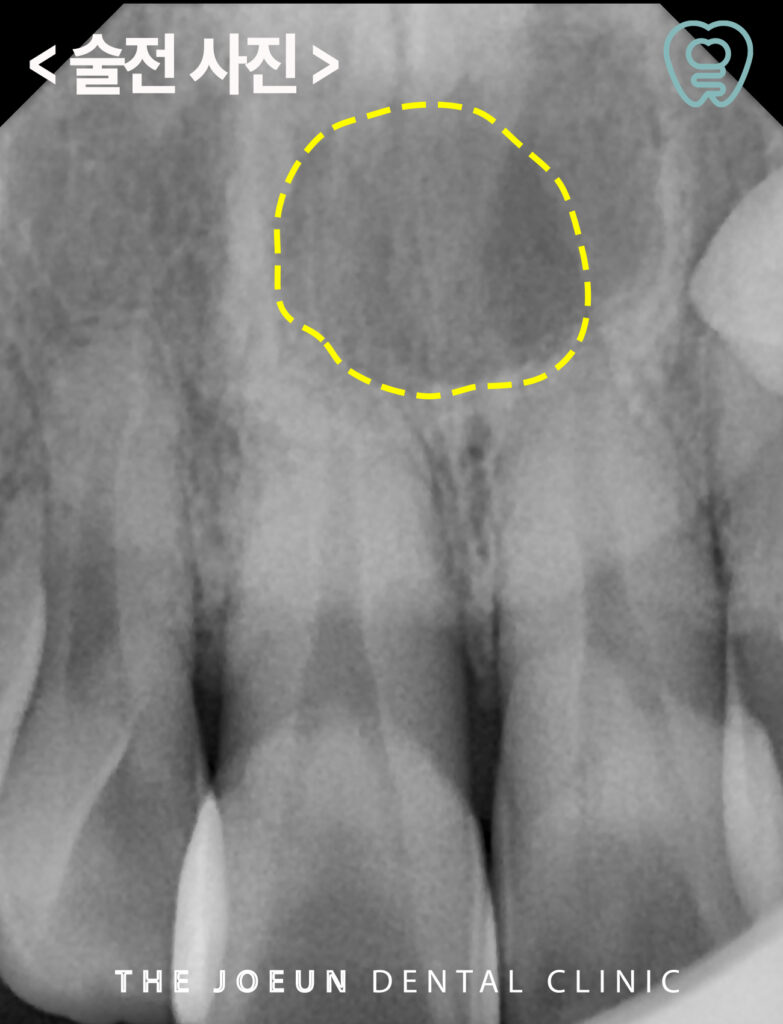

환자분께서는 입천장이 붓는 느낌이 들고 통증이 있다고 하시며 달서구치과에 내원해 주셨는데요. 파노라마를 촬영해 보았을 때, 위쪽 앞니의 뿌리 쪽으로 아주 커다란 물혹이 관찰되었는데요. 더욱 정밀한 진단을 위해 x-ray와 CT 촬영을 모두 진행하였습니다.

모든 방사선 검사에서 경계가 뚜렷이 보이는 낭종이 관찰되었고 낭종적출술을 진행하기로 계획을 수립하였습니다.